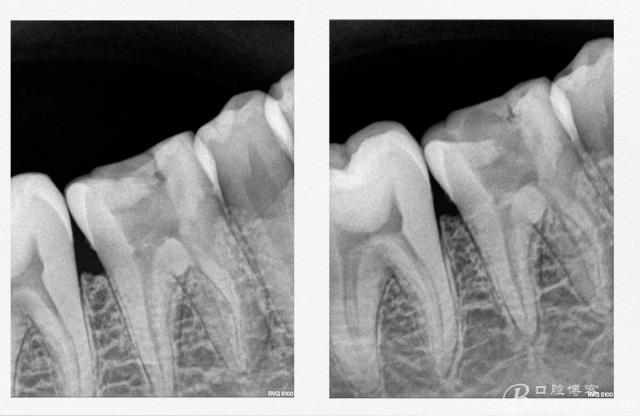

17远中邻面深龋,牙髓炎发作,本来想一次根充的结果出了意外

术前x线检查(全景片及局部小片,了解患牙基本情况)患者 男 30岁,右下

典型的牙髓炎